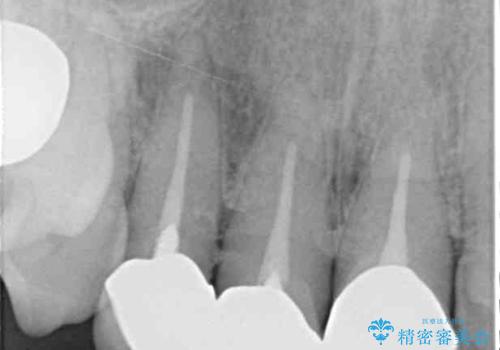

- 20年以上前に装着した前歯のメタルセラミックが不自然であることを気にして来院された患者様です。

歯肉の位置が変わり、変色した歯根が露出しているため、金属の土台をファイバーコアに交換した上で、オールセラミッククラウンにて補綴することとしました。